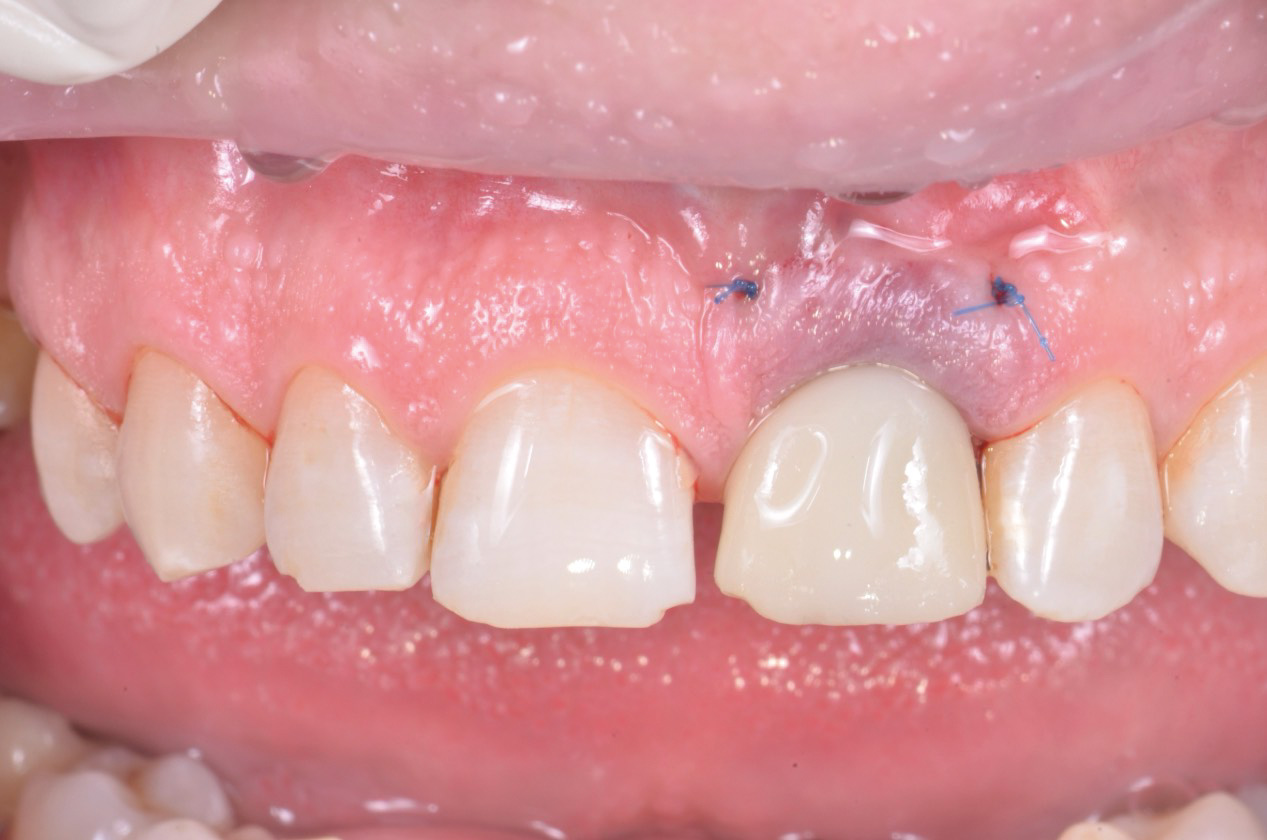

Dal momento che l’impianto presentava un torque di inserimento superiore ai 40 N/cm2 è stato possibile proseguire con il trattamento come da progetto con la protesizzazione immediata. L’elemento provvisorio è stato fissato con del composito fluido al pilastro provvisorio grazie al posizionatore stampato 3D che ha permesso di mantenere l’esatta posizione progettata a software (fig.12).

A questo punto, il provvisorio è stato rimosso e rifinito in modo da creare un profilo di emergenza che sostenesse il tessuto innestato e poi consegnato (fig.13, 14).